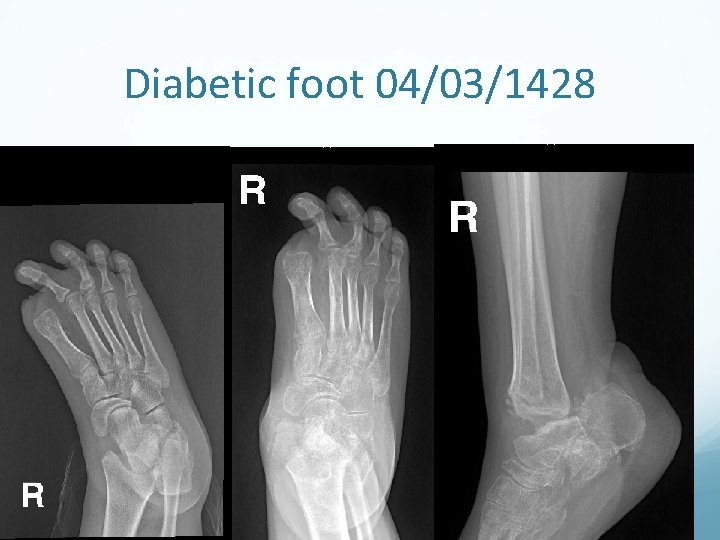

Diabetic Foot • Neuropathy (nerve damage) i. Long term diabetes or ii. Failure to control diabetes numbness, tingling and reduced sensation of the feet. Associated with Decreased circulation (neuropathy, calcification of vessels, CAD) may result in delayed healing, infections, Gangrene and Amputations

Surgery in Diabetic Foot Skilled care of wounds and ulcers in diabetic foot is required. Wound debridement, antibiotics and repeated dressing should be done. Amputations may become necessary when there is Gangrene. Toe amputation or ray amputation, forefoot amputation, below or above knee amputation.

Diabetic foot 04/03/1428